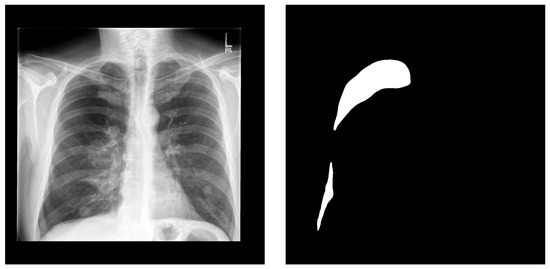

Figure 1.

A sample from the CANDID-PTX dataset. Left is the original chest X-ray and right is the corresponding pneumothorax manual segmentation.